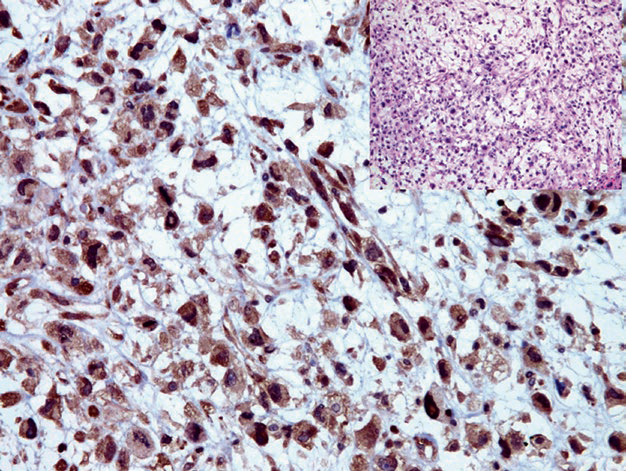

图1. 去分化脂肪肉瘤中,肿瘤细胞表达MDM2。